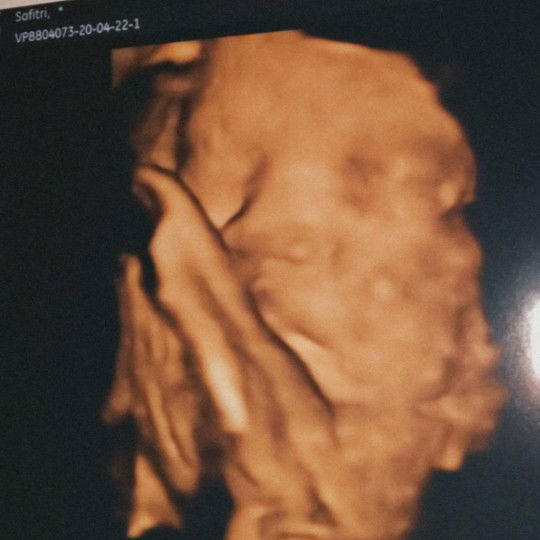

Udah 38week si dede masih betah aja di dalam perut. belum rasain mules atau tanda-tanda. Jangan betah-betah di dalam ya de ??